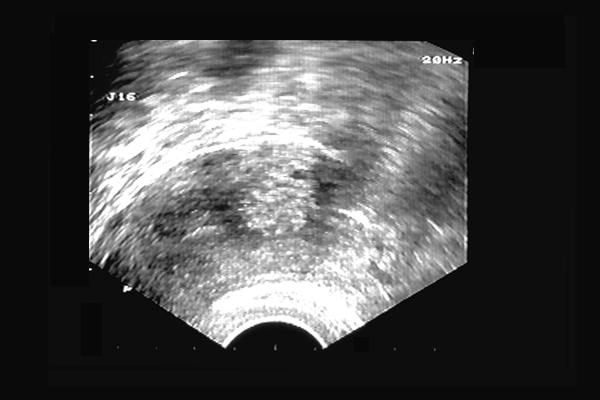

Adénomyose utérine. Zone hyperéchogène mal limitée, adénomyose "nodulaire".41 ans, ménorragies douloureuses.